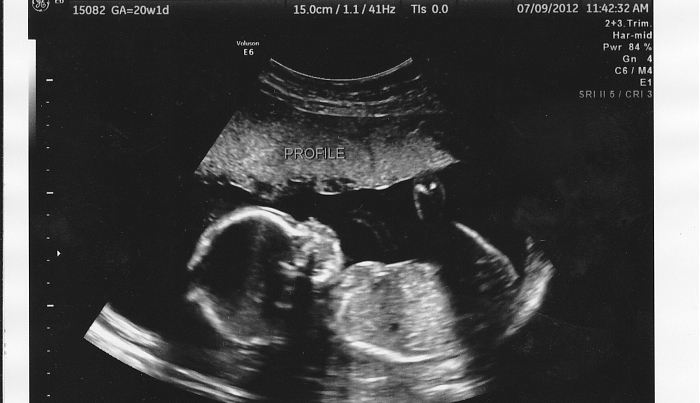

W Wielkiej Brytanii co roku dokonuje się około 200 tysięcy aborcji. Prawo brytyjskie zezwala na zabicie nienarodzonego dziecka do 24. tygodnia ciąży. Większość aborcji dokonuje się na życzenie, wskazując, że kontynuowanie ciąży stanowi ryzyko doznania urazu fizycznego lub psychicznego u ciężarnej kobiety, lub u jej dzieci i rodziny.